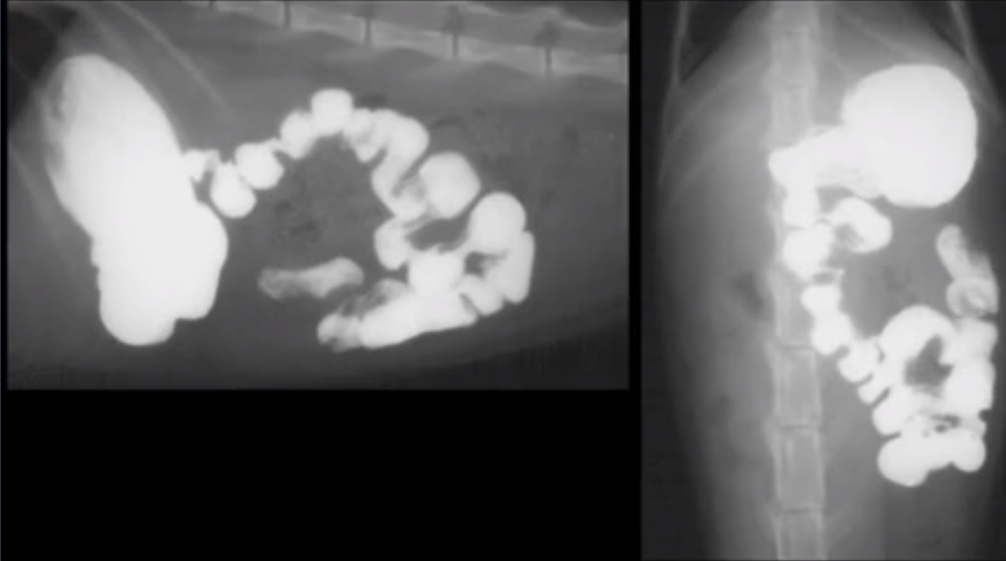

What does this image show?

Dilated uterus (no foetuses will be present until day 44)

General dilation

Ball FB with local dilation

Gravel sign of partial obstruction

Linear FB - plicated SI moved to one side of the body

FB consistently seen between views

Mass in lumen

Intussecption - long filling defect with contrast around it